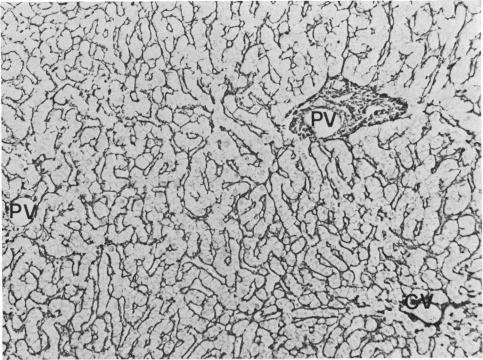

We report the cases of two renal transplant recipients suffering from idopathic portal hypertension, a condition characterised by increased portal venous pressure in the absence of both histological lesion of the liver and obstruction of the portal vein. In these two patients, perisnusoidal fibrosis, invisible by light microscopy, was demonstrated by electron microscopy; it is suggested that partial obstruction of hepatic sinusoids by perisinusoidal fibrosis could be the mechanism for increased portal venous pressure in all the patients with idiopathic portal hypertension. In these two patients, who received 6-mercaptopurine and azathioprine, perisinusoidal fibrosis might be the consequence of prolonged administration of these drugs.

我们报告了两例患有特发性门静脉高压症的肾移植受者病例,该病症的特征是在没有肝脏组织学病变和门静脉阻塞的情况下门静脉压力升高。在这两名患者中,光镜下不可见的窦周纤维化通过电子显微镜得以证实;有人提出,窦周纤维化导致的肝血窦部分阻塞可能是所有特发性门静脉高压症患者门静脉压力升高的机制。在这两名接受6-巯基嘌呤和硫唑嘌呤治疗的患者中,窦周纤维化可能是长期使用这些药物的结果。